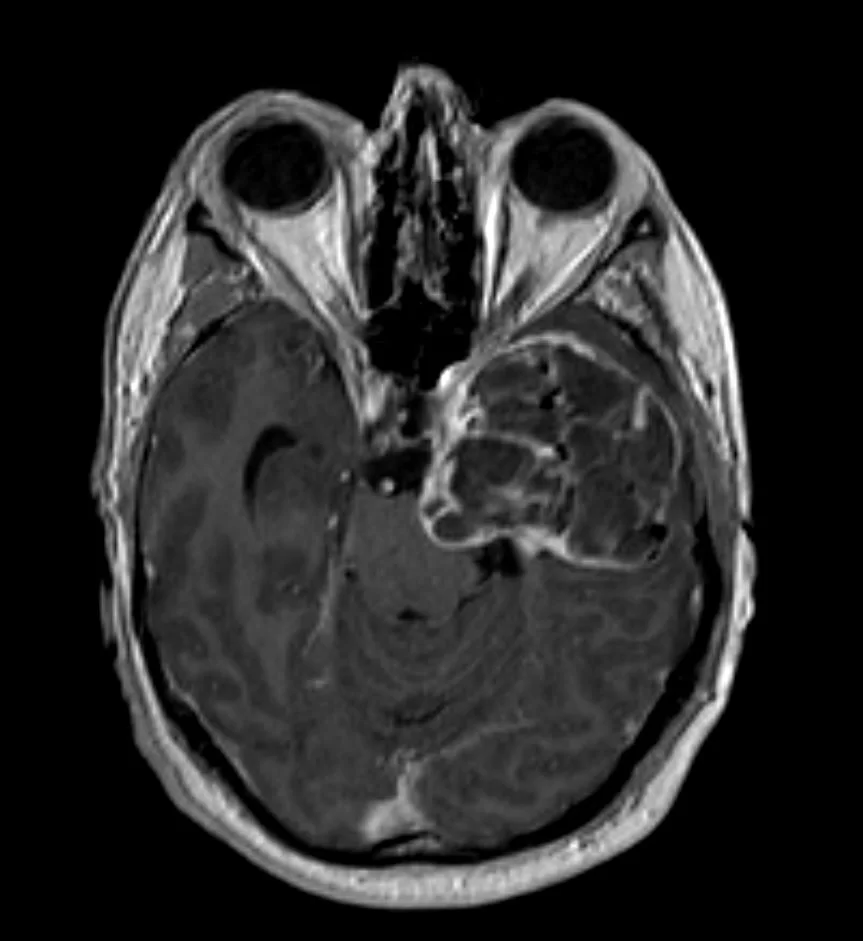

Επιδερμοειδής όγκος δεξιάς γεφυροπαρεγκεφαλιδικής γωνίας

Ασθενής 19 ετών με γνωστή χωροκατακτητική εξεργασία (επιδερμοειδες γεφυροπαρεγκεφαλιδικής γωνίας δεξιά) με προοδευτικά σημαντική αύξηση μεγέθους. Νευρολογικά ακέραιος. Ο απεικονιστικός έλεγχος με μαγνητική τομογραφία ανέδειξε